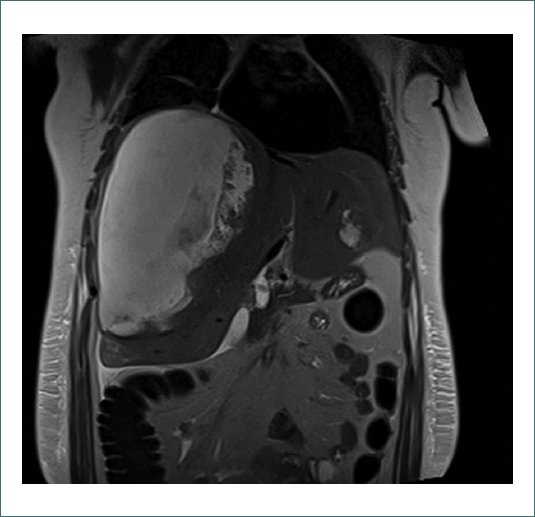

Después del procedimiento, persiste dolor de difícil control que requiere escalada analgésica siguiendo el protocolo hospitalario desde paracetamol 1g/8h + metamizol 1g/8h alternados + ibuprofeno 400mg/8h hasta PCA endovenosa (Analgesia Controlada por el Paciente) de morfina a dosis reducida (5 mg cada 10 minutos). A pesar de la optimización analgésica, la paciente sigue presentando un EVA 8 y se solicita valoración por Unidad del Dolor para un abordaje multidisciplinar. Se ajusta pauta analgésica con gabapentina en pauta ascendente hasta 600 mg/8h + duloxetina 30 mg/24 h + clonazepam 0,5 mg/24 h. Se aumenta PCA a pauta estándar (10 mg cada 10 minutos). A pesar de los ajustes previos, la paciente continúa con dolor intenso y la exploración no reporta cambios. Analíticamente la paciente presenta una buena evolución, sin signos de anemización ni elevación de parámetros inflamatorios. El perfil de transaminasas sigue una curva descendente. Se completa estudio de imagen con resonancia magnética nuclear (RMN) (Figs. 1 y 2).

Figura 2. Corte coronal de RMN hepática en secuencia T2 con saturación grasa. Se visualiza voluminoso hematoma derecho que condiciona elevación del hemidiafragma derecho. En lóbulo hepático izquierdo se visualiza adenoma que ya visualizábamos en la figura 1.